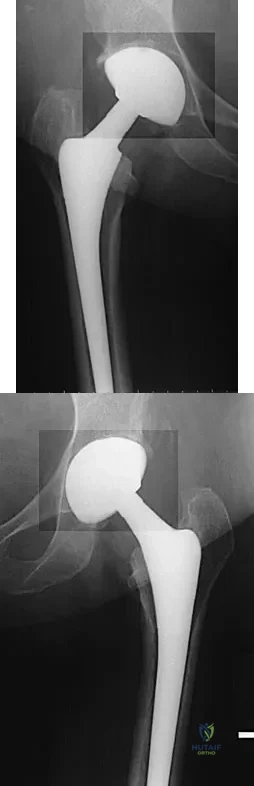

Question 80

A 68-year-old woman underwent a successful total right hip arthroplasty with a metal-on-metal articulation and cementless porous-coated components. Three months later, she underwent identical surgery on the left hip. Three months after surgery on the left hip, she reports groin pain on ambulation. Examination reveals significant groin discomfort with passive hip motion, particularly at the extremes of motion. Radiographs are shown in Figures 21a and 21b. Laboratory studies show an erythrocyte sedimentation rate of 35 mm/h and a C-reactive protein of 0.9. Aspiration yields scant growth of Staphylococcus epidermidis in the broth only, with no evidence of loosening on arthrography. A second aspiration yields scant growth of Staphylococcus epidermidis in the broth only. What is the most likely cause of the patient's pain?

Explanation